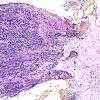

PERIPHERAL NEUROPATHY

15 NEUROPATHY ASSOCIATED WITH NEOPLASIA

1 Neoplastic Infiltration (8)